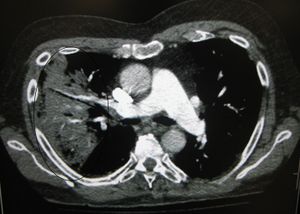

A chest X-ray showing a very prominent wedge shaped pneumonia in the right lung. | |